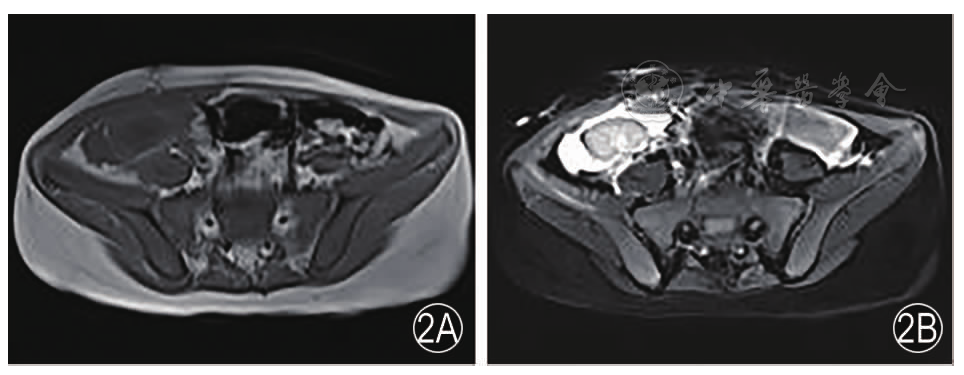

患儿男性,11岁。主诉:肾功能异常4年2月,规律腹膜透析2年。患儿4年2个月前因面色苍黄、恶心、呕吐、纳差等症状,至郑州市儿童医院就诊,查肾功能示肌酐276.7 μmol/L,尿酸314.7 μmol/L,尿素21.1 mmol/L,诊断为"慢性肾脏病4期",给予口服促红素针刺激骨髓造血、开同片、尿毒清颗粒、百令胶囊、骨化三醇等药物治疗后好转,后定期复查,2018年11月患儿出现恶心、呕吐,饮食极差,伴精神状态差,查肾功能示肌酐778.0 μmol/L,血钾7.2 mmol/L,给予血液透析治疗后规律行腹膜透析。今为求进一步诊治,患儿及家长于2021年4月9日前来我院,门诊以"慢性肾功能不全(尿毒症期)"收入院。患儿既往无肝炎、结核等传染病史,父母均体健,无家族遗传性病史。入院后患儿神志清,精神可,食欲正常,睡眠正常,大便正常,尿量约500~600 mL/d,体重无减轻。体格检查:慢性病容,贫血貌,双眼睑无水肿,双下肢水肿。实验室检查:红细胞计数3.46×1012/L,血红蛋白102.8 g/L,血小板352×109/L,红细胞压积0.32 L/L,降钙素原0.64 ng/mL,血钠132.0 mmol/L,血氯87.1 mmol/L,血镁1.1 mmol/L,尿素26.09 mmol/L,肌酐761.0 μmol/L,碱性磷酸酶630.0 U/L,N端脑钠肽前体863.0 pg/mL。肾源配型成功后患儿行同种异体肾移植术,术中将移植肾放入右髂窝内,逐层关闭切口并包扎。术中出血约50 mL,术中尿量约50 mL(供肾为心脏死亡器官捐献,热缺血时间为8 min,冷缺血时间为10 h 15 min,供肾动脉为双支动脉)。术后患儿生命体征平稳,给予三联免疫抑制治疗(他克莫司+吗替麦考酚酯+强的松),免疫诱导方案为甲强龙针0.25 g+兔抗人胸腺细胞免疫球蛋白针12.5 g。术后连续3天查肾功能血肌酐异常升高(761.0、862.0、970.0 μmol/L),行超声检查评估移植肾功能示移植肾回声均匀,集合系统无分离,CDFI:血流灌注不佳,移植肾静脉血流充盈不佳(图1);移植肾周可及范围约3.0 cm×1.5 cm液性暗区。行肾脏MRI平扫示:右侧髂窝内移植肾皮髓质分界欠清晰,肾门朝向后内侧,肾内集合系统结构紊乱,周围见大片状T1WI低信号、T2WI高信号(图2)。给予激素冲击治疗、调整免疫抑制剂用量等一体化治疗后效果不明显。行移植肾超声造影:经肘静脉以团注方式注射超声造影剂(Sonovue,声诺维)0.5 mL后,随即注入5 mL生理盐水,于5 s开始右侧髂动脉内出现造影剂灌注,同时移植肾动脉内未见明显超声造影剂微气泡灌注,观察60 s,移植肾动脉主干及各级动脉均未见显影,考虑移植肾动脉栓塞,移植肾无灌注(视频1)。患儿行移植肾切除术,术中见移植肾周大量浓白色脓液,移植肾动静脉管壁颜色灰白,移植肾动脉内血栓形成。术后病理示(右侧移植肾)肾实质凝固性坏死(图3)。目前患儿给予抗感染,抗病毒,规律腹膜透析等对症及支持治疗,规律随访,等待肾源配型。本文经郑州大学第一附属医院科研项目伦理审查委员会审查证明,伦理审查编号:2021-KY-102。

图2 肾脏MRI示右侧髂窝内移植肾皮髓质分界欠清晰,肾门朝向后内侧,肾内集合系统结构紊乱,周围见大片状T1WI低信号(2A)、T2WI高信号(2B)